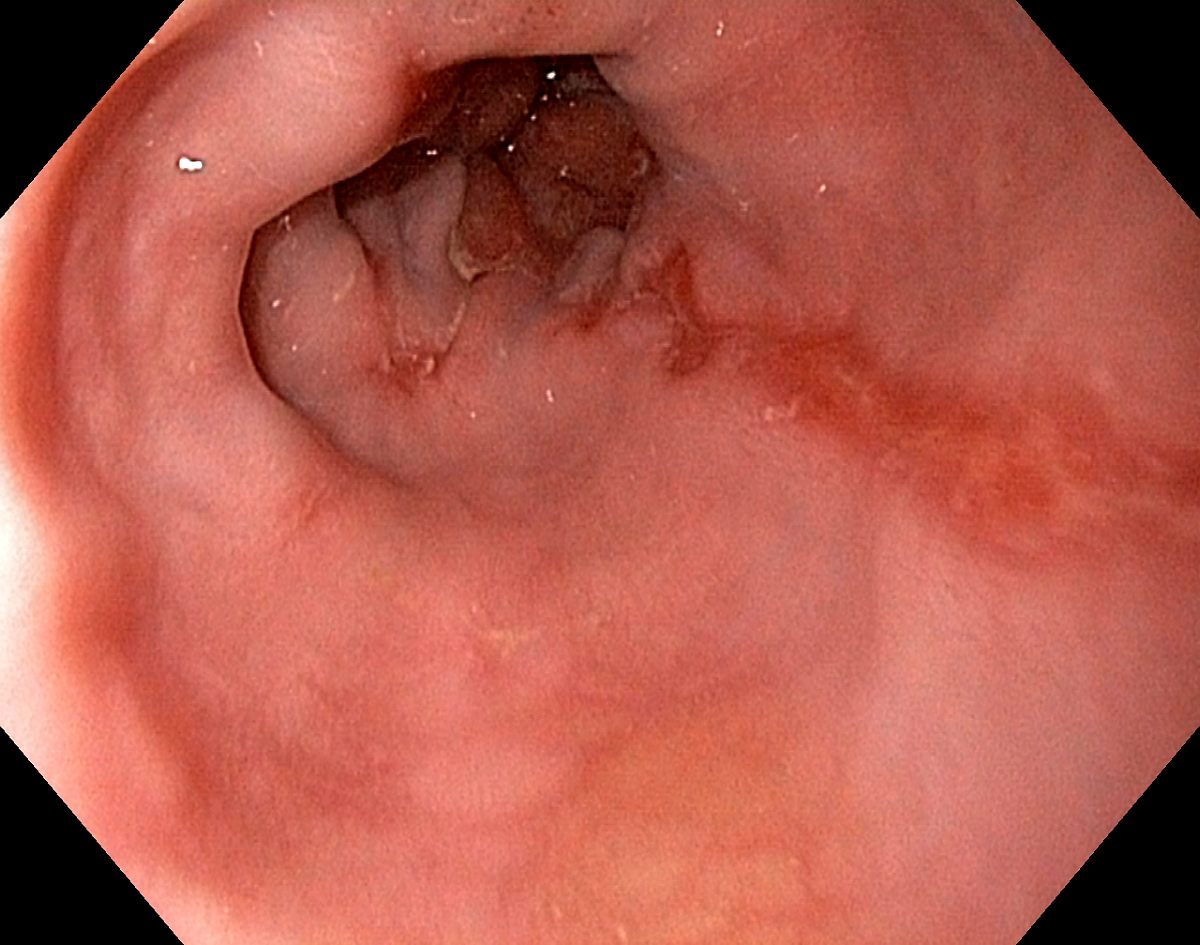

Reflux oesophagitis grade D according to the Los Angeles classification